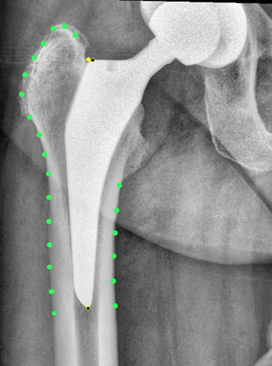

Hip stem migration (subsidence) was evaluated on anteriorposterior radiographs of the pelvic in a standing position with a film-focus-distance of 115 cm performed 5 days, 3 months and two years postoperative. The validated software “FXA” of the independent imaging core lab (RAYLYTIC, Leipzig, Germany) was used [26-28]. The software matches two images (24 months and 3 months vs. 5 days postop) using a normalized 2D grayscale cross-correlation algorithm in an iterative process using the evolutionary optimization algorithm CMA-ES [29]. Moreover, the radiographs were analyzed for radiolucent lines around the stem. The radiographs were analyzed retrospectively. The following parameters were measured on the postoperative radiographs (Figure 2,3): The Canal Flare Index (CFI), the Canal Fill Ratio (CFR), the Stem Angulation (SA) and calculated as potential influencing factors for subsidence as well as the clinical parameters: gender, weight, BMI, age and stem size.

Figure 3b: Case example with FXA software to analyze the subsidence. Fig. 3a: five days postoperative, Fig. 3b: two years postoperative